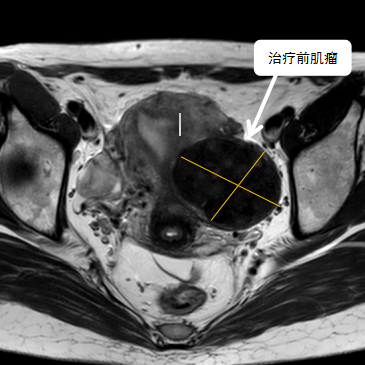

術(shù)前影像資料

經(jīng)過(guò)兩個(gè)月的藥物預(yù)處理,完善術(shù)前準(zhǔn)備,治療當(dāng)天陳主任帶領(lǐng)團(tuán)隊(duì)在3.0T磁共振清晰圖像引導(dǎo)下對(duì)子宮肌瘤進(jìn)行精準(zhǔn)消融,患者全程清醒,沒(méi)有明顯疼痛,經(jīng)過(guò)1個(gè)多小時(shí)的精細(xì)操作,手術(shù)非常成功,消融率接近90%,內(nèi)膜未見(jiàn)損傷!觀察一個(gè)小時(shí)后患者即自行回家。